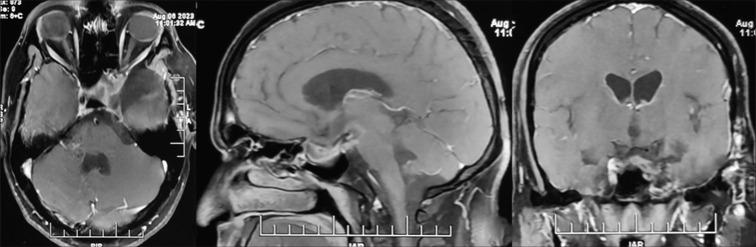

We report here a case of giant amyloidogenic prolactinoma in a 32-year-old male patient who had a very atypical presentation in terms of clinical, radiological, and pathological features and responded to dopamine agonist therapy like a normal prolactinoma.

我们在此报告一例32岁男性患者的巨大淀粉样变性泌乳素瘤病例,该病例在临床、影像学和病理学特征方面具有非常不典型的表现,并且对多巴胺激动剂治疗的反应与正常泌乳素瘤相同。